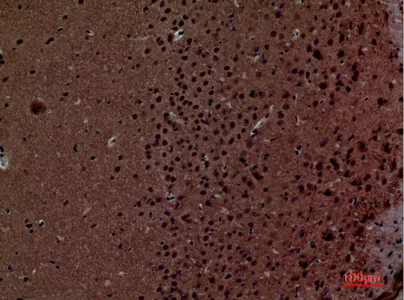

FGF20 Rabbit Polyclonal Antibody

Cat: APRab00516

Size1:50μL Price1:$150

Size2:100μL Price1:$280

Size3:500μL Price1:$280

Application:WB,IHC-P,ELISA

Reactivity:Human,Mouse,Rat

Conjugate:Unconjugated

Gene Name:FGF20

Size2:100μL Price1:$280

Size3:500μL Price1:$280

Application:WB,IHC-P,ELISA

Reactivity:Human,Mouse,Rat

Conjugate:Unconjugated

Gene Name:FGF20